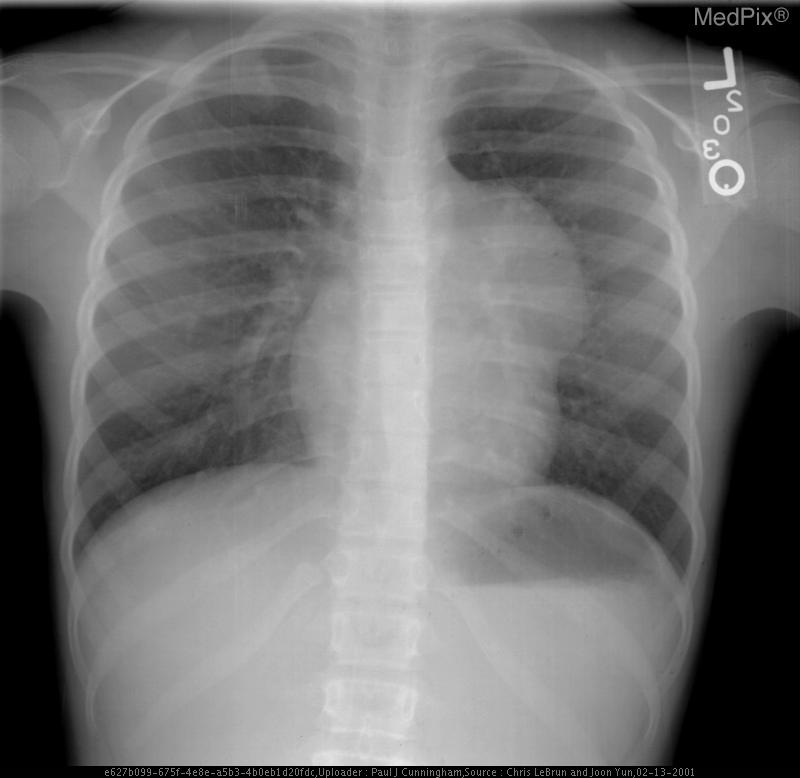

Mediastinal Teratoma

• Age: 9

• Sex: Female

• Modality: X-ray

• Region: Chest

• Diagnosis: Mediastinal Mature Teratoma

1) Findings:

- Frontal chest radiograph, properly oriented: image-left = patient-right.

- Cardiac silhouette is mildly displaced toward the image-right (patient-left), suggesting mass effect from a mediastinal lesion.

- A well-circumscribed, rounded opacity occupies the image-left (patient-right) upper mediastinum, with smooth margins.

- The lesion shows heterogeneous internal density, including areas of relative lucency (suggesting fat) and opacity (possibly soft tissue or calcification).

- Lungs otherwise clear without focal consolidation or effusion.

- Bony thorax intact with no visible rib destruction or vertebral abnormality.

- Trachea slightly deviated toward image-right (patient-left), consistent with mild mediastinal shift.

- Diaphragms symmetric; cardiopericardial silhouette otherwise unremarkable except for mass effect.

2) Most likely diagnosis and why:

Anterior mediastinal teratoma. The well-defined, heterogeneous mass in the anterior mediastinum with soft tissue and possible fatty or calcific elements is characteristic of a mediastinal teratoma. Leftward (patient-left) cardiac displacement and tracheal shift support a space-occupying lesion in the anterior mediastinum. Context consistency: Consistent. The reported age (child) and sex (female) align with a known demographic pattern for benign mediastinal teratoma. Confidence: 90%.